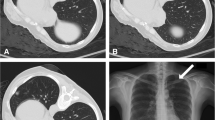

Middle lobe, lingular, and lower lobe lesions were categorized as “lower locations”; upper lobe lesions, as “upper locations” [11]. Lesion size was measured as the largest diameter of the sampled lesion in the previous CT images. The depth of the lesion was gauged as the length of the needle track from the punctured pleura to the edge of the lesion sampled. The needle-pleural angle was calculated on the transverse 3-mm section in the craniocaudal dimension, according to the method suggested by Ko et al. [6]. It was defined as the minimum angle formed by a line tangent to the pleura at the puncture point and a line drawn along the needle (Fig. 1) [6]. Pneumothorax was evaluated by CT scan after biopsy, as the largest separation between the visceral and parietal pleura. Less than or equal to 1 cm was categorized as “minor pneumothorax”; greater than 1 cm but less than or equal to 2 cm, as “intermediate pneumothorax”; greater than 2 cm, symptomatic or chest drainage catheter insertion needed, as “severe pneumothorax” [12].

a CT-guided core needle biopsy of a solitary suspected lesion in the right lower lobe, in a 56-year-old male patient with 6 pack-years smoking. b Showed the biopsy needle (arrow) inserted within the lesion, which was later pathologically confirmed to be pulmonary adenocarcinoma. The patient was in lateral position on the CT table. The needle-pleural angle (curved white arrow), which was the minimum angle formed by a line tangent to the pleura at the puncture point and a line drawn along the needle, was 63°. The length of the needle track from the pleura to the lesion was 14.4 mm. The dwell time was 660 s. c CT image after the removal of the biopsy needle showed pneumothorax (arrowhead), which continued to increase until the chest drainage catheter was inserted

PCNBs were performed by one intervention team led by Prof. C. L. (7 years of experience in CT-guided needle biopsy), using only one type of needle, 17-gauge coaxial introducer and 18-gauge automated cutting needle (Biopince, Argon Medical Devices, Frisco, Texas). All the biopsies were carried out according to the standard protocol. All patients underwent enhanced CT before the biopsy. Averting obvious emphysema or bulla, the safest and shortest route from the chest wall to solid part of the lesion was chosen to determine the supine, prone or lateral position of the patient on the CT table. All patients were given intravenous indwelling needles, allowing for the infusion of rescue drugs if necessary. The patients were instructed to breathe shallowly and avoid moving, coughing, speaking or deep breathing during and 3 h after the procedure. If the biopsy route needed to be changed, the patient's position could also be changed. After aseptic technique and local anesthesia with 1% lidocaine, the introducer needle was inserted. The needle is inserted rapidly during pleural puncture, and the needle is withdrawn slowly after the biopsy. Rapid insertion at breath-hold can form a precise puncture point, while slow extraction of the guide needle can make the elastic lung tissue seal the pleural hole. Then the position of the coaxial introducer was determined by CT scan. If the introducer was correctly located within the periphery of the lesion, the biopsy was performed to obtain sufficient tissue samples. The representative images of the CT-guided PCNB are shown in Fig. 1. After slowly removing the needle, CT scan was performed to evaluate the complications. The patient was then asked to rest for 24 h. Patients with pneumothorax or bleeding were monitored in the inpatient ward. Patients with intermediate or severe pneumothorax were arranged to have a follow-up CT scan to determine its stability. If patients had pneumothorax with symptoms of respiratory distress or shortness of breath, a closed thoracic drainage (8 Fr. pig-tail) was performed.